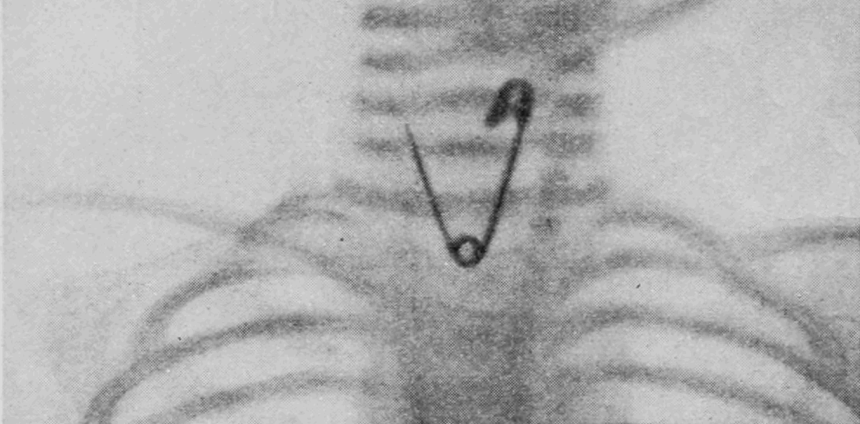

Os métodos tradicionalmente usados para localizar esse tipo de objeto em organismos são os exames de raios X tradicionais, tomografias computadorizadas ou radioscopias. Mas, embora eles identifiquem a região geral onde o material está, não têm resolução espacial para indicar a posição e profundidade exatas. Além disso, não há referências anatômicas viáveis, pois os objetos em geral estão alojados em tecidos moles, transparentes aos raios X. Uma desvantagem adicional é que expõem pacientes e equipe médica à radiação.

Como a agulha perdida no caso da criança era feita de material ferromagnético (aço), usamos os sensores magnéticos (magnetômetros) originalmente destinados aos estudos de Biomagnetismo – chamados de SQUIDs – capazes de detectar campos magnéticos muito fracos. Assim, trabalhamos no desenvolvimento de um método de localização que foi capaz de identificar a posição exata do objeto no corpo em três dimensões: profundidade, orientação e centro. Os parâmetros foram usados em combinação com a projeção do corpo estranho na pele para planejar o procedimento e definir a incisão cirúrgica.

O resultado foi extremamente animador. Além de ajudar aquela criança, depois validamos experimentalmente essa técnica em outros seis casos de remoção bem sucedida de agulhas de costura perdidas em outras pessoas. Em todos os casos, foi possível localizar com exatidão os objetos, reduzindo significativamente o tempo cirúrgico, e garantindo o sucesso do procedimento para remoção.